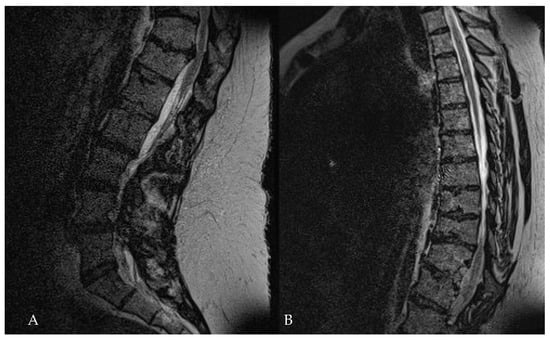

Surgical Treatment of Calcified Thoracic Herniated Disc Disease via the Transthoracic Approach with the Use of Intraoperative Computed Tomography (iCT) and Microscope-Based Augmented Reality (AR)

5.1. Surgical Technique and Outcome for Resection of Calcified Thoracic Disc